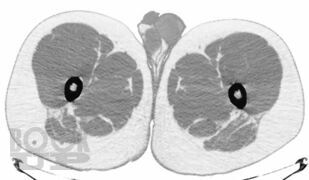

В руководстве подробно описана методология проведения компьютерно-томографического исследования при эндокринологических заболеваниях, рассмотрены основные диагностические аспекты и возможности компьютерной томографии при образованиях надпочечников, щитовидных и паращитовидных желез, гипофиза, заболеваниях костей и офтальмопатии. Продемонстрированы также возможности современной мультиспиральной компьютерной томографии в диагностике эндокринопатий. Издание иллюстрировано большим количеством компьютерных томограмм.